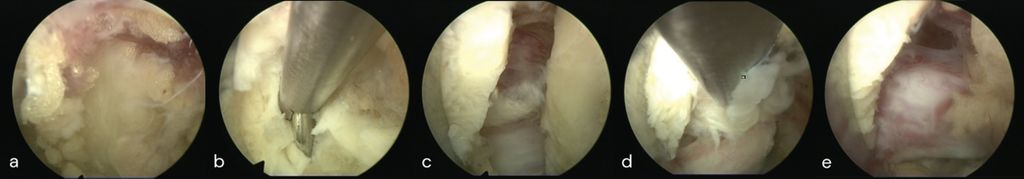

Lumbale vollendoskopische Diskektomie

Die Benefits erzielt die endoskopische Technik bei gering invasiven und technisch niedrig komplexen Eingriffen der Lendenwirbelsäule. Die interlaminäre (IL) und die transforaminäre (TF) endoskopische Diskektomie sind in Bezug auf radikuläre Schmerzreduktion und das funktionelle Outcome der offenen Mikrodiskektomie gleichwertig und hocheffektiv. Ruetten et al. konnten eine signifikant geringere Rate postoperativer Lumbago-Symptomatik nachweisen. Vorteile ergeben sich durch kürzere Operationszeiten, reduzierten Blutverlust, niedrigere Komplikations- und Revisionsraten sowie einen geringeren postoperativen Analgetikabedarf.16 In einer prospektiven randomisierten Studie an 143 Patienten zeigten sich im FE-Arm im 2-Jahres-Follow-up ein kürzerer stationärer Aufenthalt und eine deutliche Reduktion radikulärer Schmerzen im Vergleich zur offenen Mikrodiskektomie. Eigene Daten bestätigen diese Ergebnisse mit einer 90-Tage-Wiederaufnahmerate von lediglich 2% und einer mittleren Aufenthaltsdauer von 2,6 Tagen.17 Die Rezidivrate hängt sowohl von patientenbezogenen als auch von technischen Faktoren ab.18 Im direkten Vergleich ist die endoskopische Diskektomie der offenen Technik hier nicht unterlegen. Abbildung 4 zeigt die endoskopische Sicht einer interlaminären Diskektomie L5/S1 rechts (a–e) mit Darstellung des Sequesters (c, d) und der dekomprimierten Nervenwurzel S1 (e).